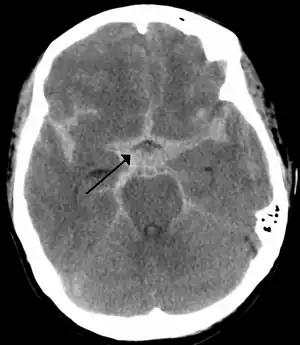

Once suspected, intracranial aneurysms can be diagnosed radiologically using magnetic resonance or CT angiography.[18] But these methods have limited sensitivity for diagnosis of small aneurysms, and often cannot be used to specifically distinguish them from infundibular dilations without performing a formal angiogram.[18][19] The determination of whether an aneurysm is ruptured is critical to diagnosis. Lumbar puncture (LP) is the gold standard technique for determining aneurysm rupture (subarachnoid hemorrhage). Once an LP is performed, the CSF is evaluated for RBC count, and presence or absence of xanthochromia.[20]

CT angiography showing aneurysm measuring 2.6 mm in diameter at the anterior communicating artery

CT angiography showing aneurysm measuring 2.6 mm in diameter at the anterior communicating artery